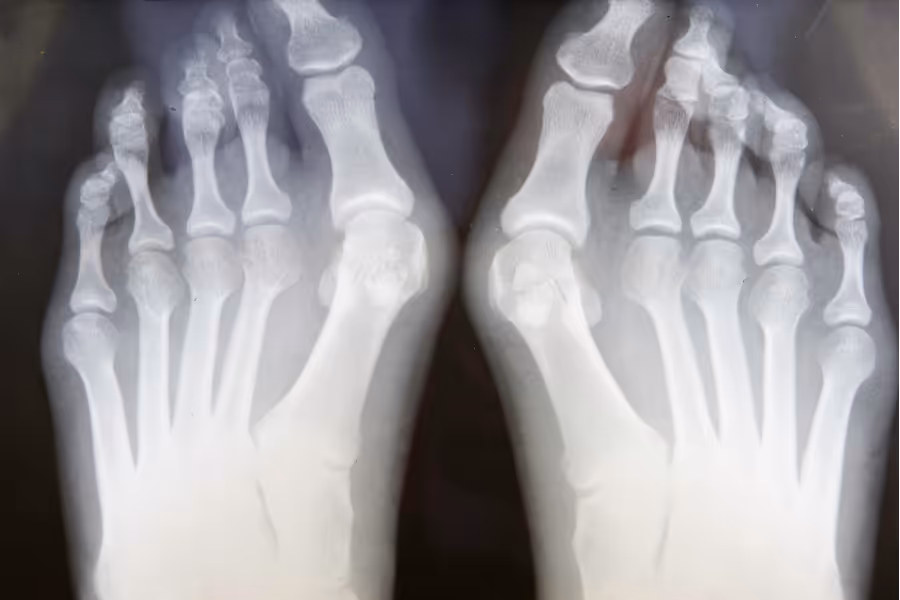

Canadians frequently look for private solutions when foot or ankle pain makes every step a challenge. Waiting over a year for fusion or reconstruction surgery can lead to worsening deformities, altered gait mechanics that affect the hips and back, and a total loss of independence and mobility.

Foot and ankle surgeries are intricate medical procedures accompanied by substantial costs. We recommend reviewing several surgeon profiles from all over the country. Going private means choice. Consider reaching out and speaking with multiple surgeons to determine who is best equipped to restore your stability and feels best for you.